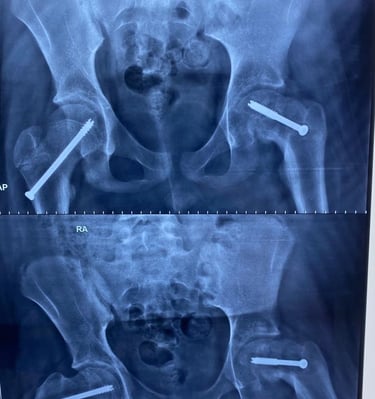

Galeria Médica

Imagens de atendimentos e procedimentos em ortopedia e traumatologia.

* Fotos autorizadas pelos pacientes para uso neste site.